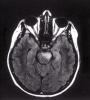

Varón de 20 años con antecedentes personales de retraso del crecimiento y crisis comiciales desde la infancia y familiares de fallecimiento de abuela materna por enfermedad muscular no filiada que ingresa por ceguera bilateral de origen cortical. A la...

Neurología: Epilepsia | OtrosEtiología: Genético / idiopáticoDiagnóstico final: Síndrome MELASNivel de certeza: